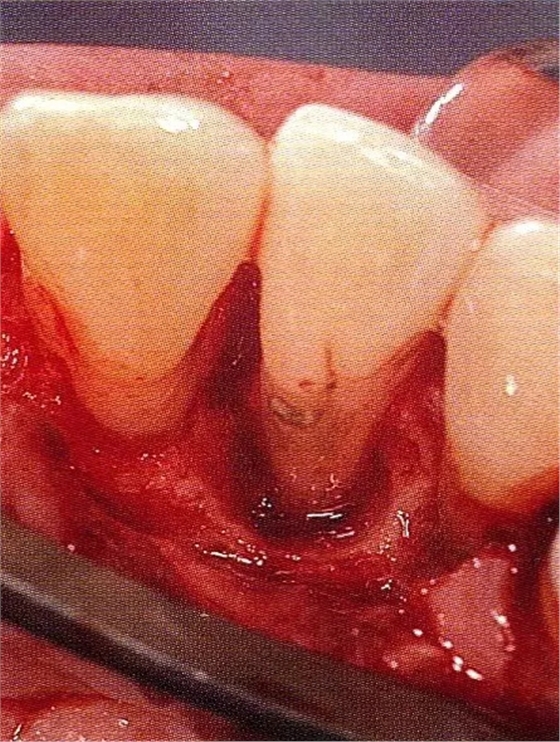

▲圖7-4術(shù)后1年2個(gè)月再翻開看的情況。與圖7-1的骨缺損狀態(tài)相比可知形成了臨床性骨再生。

▲圖7-5此狀態(tài)下,左下5的遠(yuǎn)中存在牙槽骨不平整,因此進(jìn)行了骨修整。同時(shí),將骨膜留存,進(jìn)行了齦瓣根尖側(cè)移動(dòng)術(shù),去除了牙周袋。